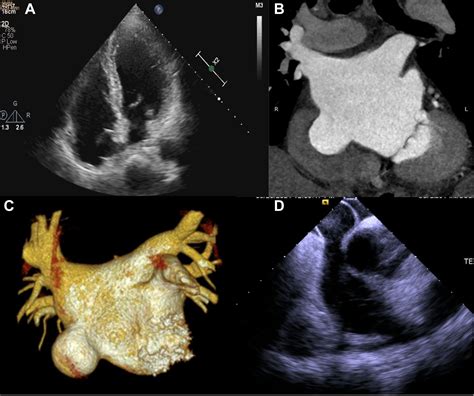

• Echocardiogram: This ultrasound test provides detailed images of the heart's structure and function, allowing doctors to visualize the aneurysm.

• Cardiac MRI: Magnetic resonance imaging offers high-resolution images of the heart, providing a comprehensive view of the aneurysm and its impact on heart function.

• Transesophageal Echocardiogram (TEE): This more invasive procedure involves inserting a probe down the throat to get a clearer view of the heart's structures.